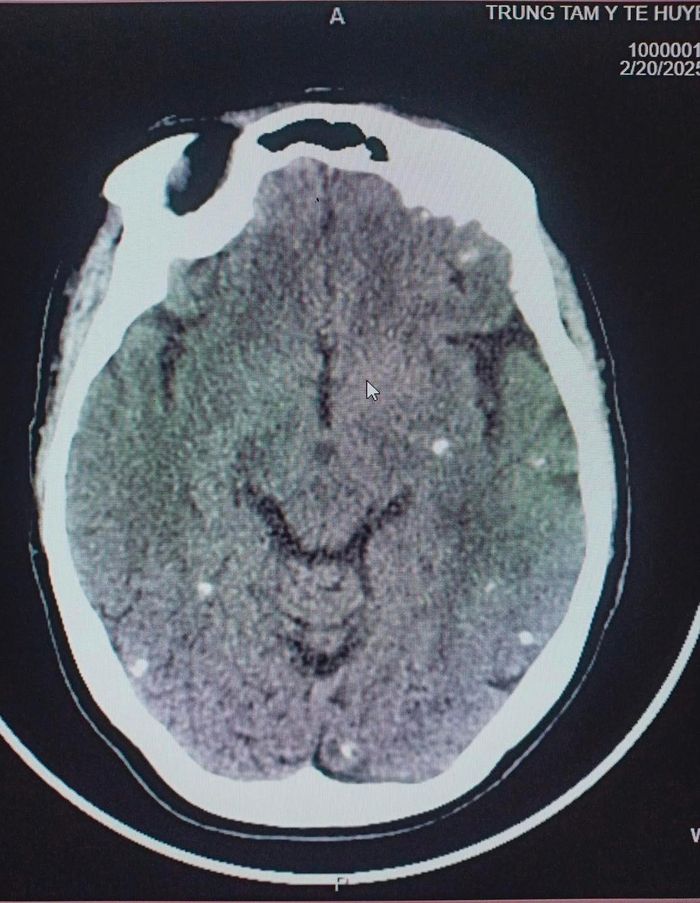

Người bệnh nhập viện với biểu hiện co giật cơ vùng mặt. Kết quả chụp CT khiến bác sĩ không khỏi bất ngờ khi phát hiện sán xuất hiện dày đặc trên khắp cơ thể.

Sán não chi chít trong cơ thể người bệnh trên phim chụp CT. Ảnh: Trung tâm Y tế huyện Tân Sơn.